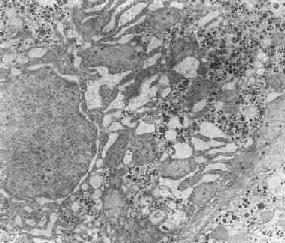

在由各种原因引起的细胞变性和坏死过程中,粗面内质网的池一般出现扩张,较轻的和局限性的扩张只有在电镜下才能窥见,重度扩张时则在光学显微镜下可表现为空泡形成,电镜下有时可见其中含有中等电子密度的絮状物。在较强的扩张时,粗面内质网同时互相离散,膜上的颗粒呈不同程度的脱失。进而内质网本身可断裂成大小不等的片段和大小泡(图1-6)。这些改变大多见于细胞水肿时,故病变不仅见于内质网,也同时累及Golgi器、线粒体和胞浆基质,有时甚至还累及溶解体。

图1-6肝细胞粗面内质网扩张